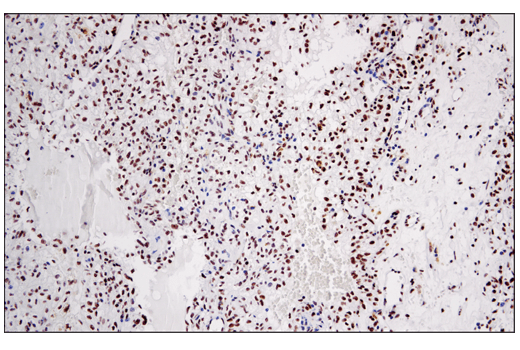

Immunohistochemical analysis of paraffin-embedded human ovarian serous carcinoma using Phospho-DNA-PKcs (Ser2056) (E9J4G) Rabbit mAb.

undefined Image 7: PhosphoPlus<sup>®</sup> DNA-PKcs (Ser2056) Antibody Duet

Immunohistochemical analysis of paraffin-embedded human renal cell carcinoma using DNA-PKcs (E6U3A) Rabbit mAb.

undefined Image 8: PhosphoPlus<sup>®</sup> DNA-PKcs (Ser2056) Antibody Duet

Immunohistochemical analysis of paraffin-embedded human lung squamous cell carcinoma using DNA-PKcs (E6U3A) Rabbit mAb.

undefined Image 9: PhosphoPlus<sup>®</sup> DNA-PKcs (Ser2056) Antibody Duet